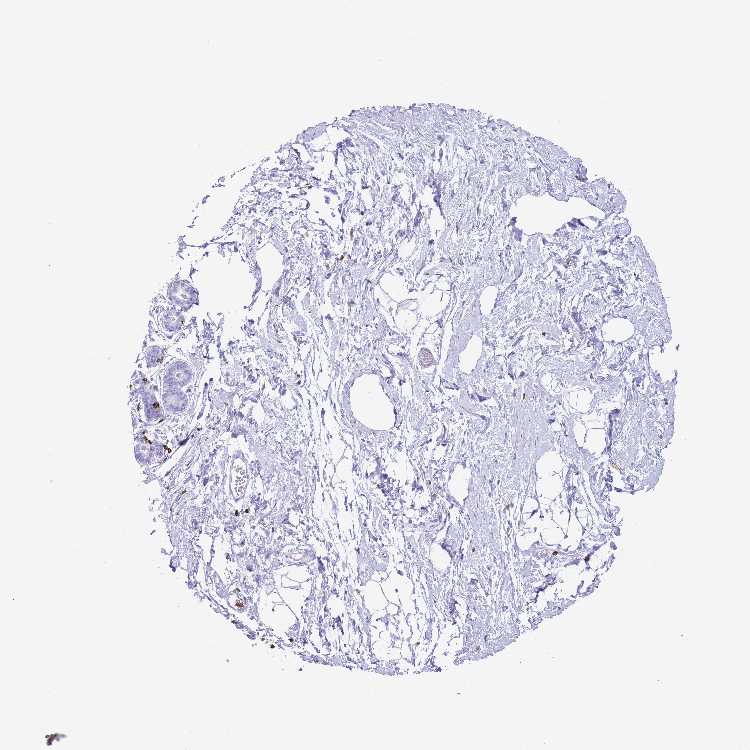

CORO1A